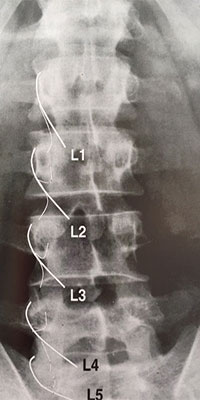

El procediment s’ha de realitzar en un quiròfan, per mantenir l’asepsia i garantir una precisió absoluta en la col·locació de la cànula, utilitzant control radiològic per visualitzar exactament la zona d’introducció.

La Radiofreqüència cervical es pot realitzar en totes les articulacions facetàries, com es mostra a la figura, en els nivells C4, C5, C6, C7 i T1.

L’objectiu del procediment és aplicar la radiofreqüència a la branca dorsal del nervi raquidi posterior, que és responsable de la innervació de l’articulació facetària.